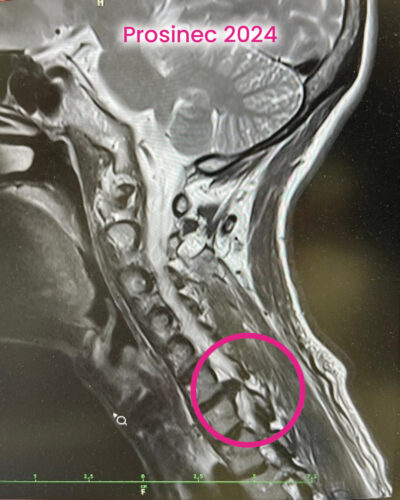

Bolest krční páteře: příčiny a léčba bez operace

Před rokem přišla nenápadná prosba.

„Mám kamarádku. Je aktivní, sportuje… ale má obrovské bolesti krční páteře. Operaci nechce. Vzala byste si ji do péče?“